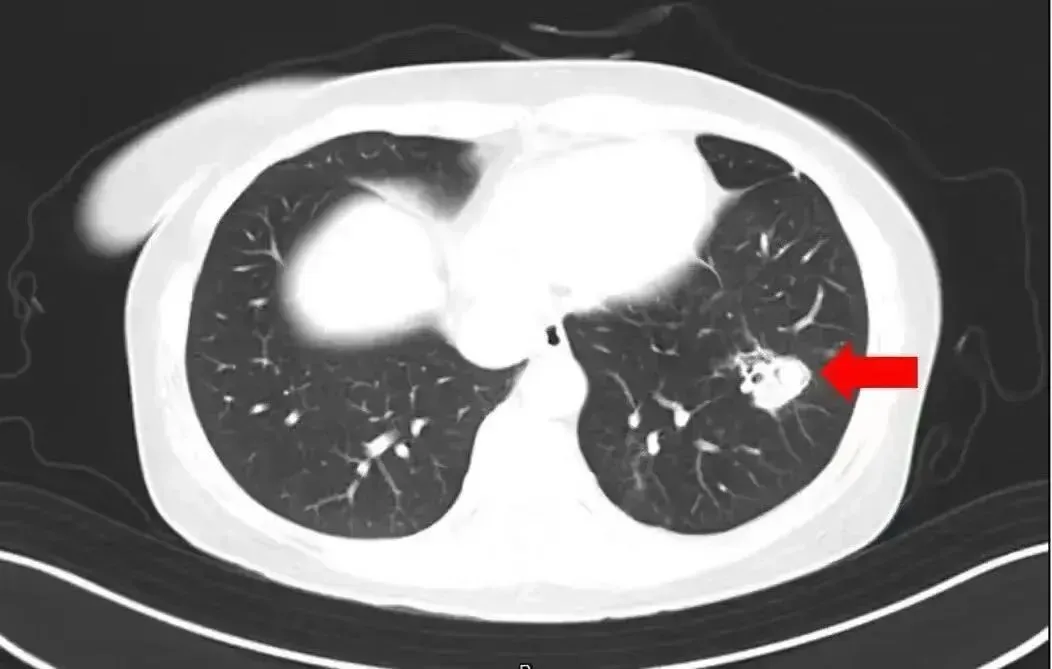

近日,有一条新闻激励网友善良:河南郑州又名6岁女孩奴婢家东说念主对故乡屋子进行清扫,随后就运行合手续发热。经病院搜检,发现其脑部被真菌侵蚀出好多个“空泛”。罪魁罪魁,即是老屋子里霉变粉尘中的“烟曲霉”。

北京佑安病院感染空洞科主任医师李侗曾先容,关于免疫力低下的东说念主,吸入了这些真菌,就会发病引起肺部的病变——曲霉肺炎。因为它是通过呼吸说念感染的,插足血液后不错扩散到全身。大脑因为血供最丰富,是以亦然真菌最容易侵扰的器官。